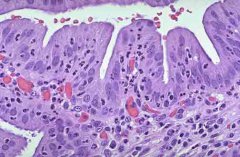

膽囊炎是細菌性感染或化學性刺激(膽汁成分改變)引起的膽囊炎性病變,為膽囊的常見病。在腹部外科中其發(fā)病率僅次于闌尾炎,本病多見于35~55歲的中年人,女性發(fā)病較男性為多,尤多見于肥...